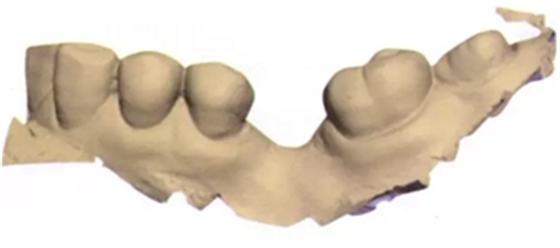

在此次就診中,也用TRIOS掃描儀(3Shape;圖2與圖3b-d)掃描左側(cè)上下頜骨和上下牙弓并進行咬合重建。只要把所有的診斷信息收集起來,第二天就可以復(fù)診治療。

將從CBCT中獲得的數(shù)字掃描文件和DICOM文件導(dǎo)入到Implant Studio軟件中(3Shape),一種新的空間技術(shù)可以創(chuàng)建口腔內(nèi)真實情況的三維重疊圖像和放射圖片。Implant Studio中的修復(fù)性設(shè)計工具可用來在修復(fù)表面圖片上創(chuàng)建一個處于理想修復(fù)位置的符合功能性和美觀性的虛擬牙冠(圖4a-d)。